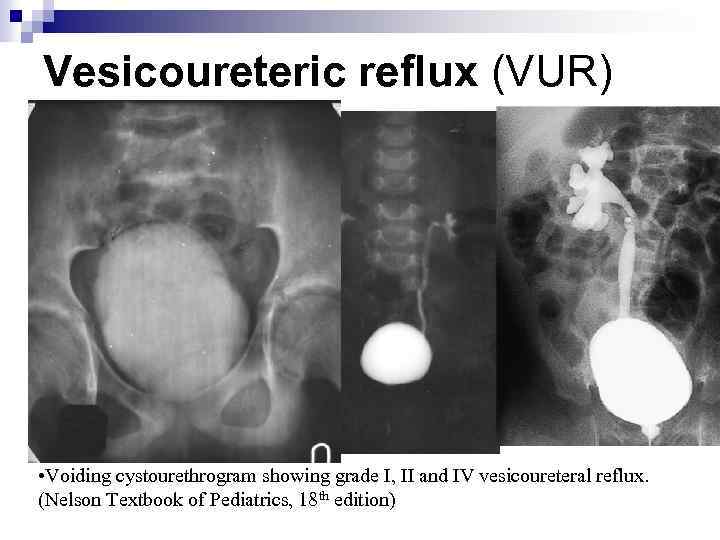

Vesicoureteric reflux (VUR) Reflux severity is graded using the International Reflux Study Classification of I to V and is based on the appearance of the urinary tract on a contrast voiding cystourethrogram (VCUG).

Vesicoureteric reflux (VUR) Reflux severity is graded using the International Reflux Study Classification of I to V and is based on the appearance of the urinary tract on a contrast voiding cystourethrogram (VCUG).

Vesicoureteric reflux (VUR) G Grage I II IV V The higher the reflux grade, the greater the likelihood of renal injury. Reflux severity is an indirect indication of the degree of abnormality of the ureterovesical junction.

Vesicoureteric reflux (VUR) G Grage I II IV V The higher the reflux grade, the greater the likelihood of renal injury. Reflux severity is an indirect indication of the degree of abnormality of the ureterovesical junction.

Vesicoureteric reflux (VUR) • Voiding cystourethrogram showing grade I, II and IV vesicoureteral reflux. (Nelson Textbook of Pediatrics, 18 th edition)

Vesicoureteric reflux (VUR) • Voiding cystourethrogram showing grade I, II and IV vesicoureteral reflux. (Nelson Textbook of Pediatrics, 18 th edition)